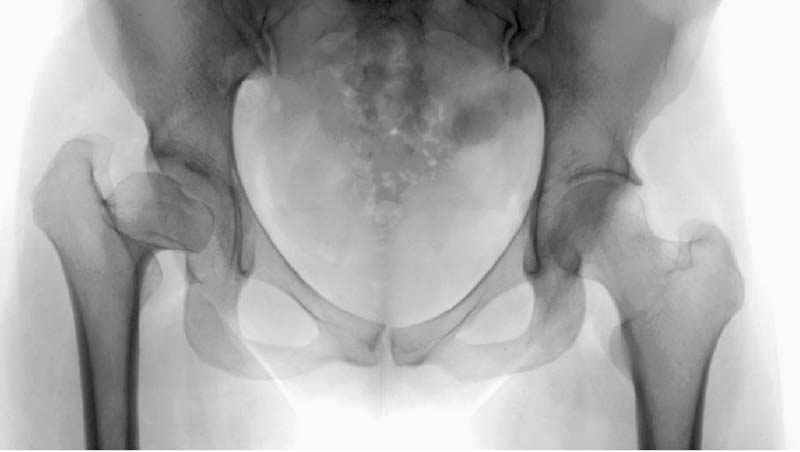

Рис.1 Трехмерная модель тазобедренного сустава с аналогом связки головки бедра. Заметно, что из торца головки выходит капроновый шнур, который с одной стороны прикрепляется к ножке бедренной части модели, а другой его конец, проходя через головку и прикрепляется к вертлужной части модели. Динамометр оказывается не нагруженным, так как аналог связки головки бедра замыкает подвижный узел модели во фронтальной плоскости.